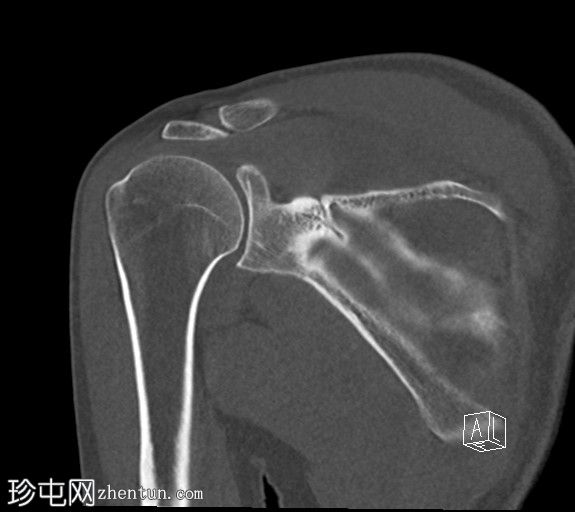

冠状位

非增强

CT显示肱骨头后外侧缘存在缺损及骨碎片,提示Hill-Sachs损伤。

右侧肩胛盂前下缘可见一小块骨碎片,提示Bankart损伤。